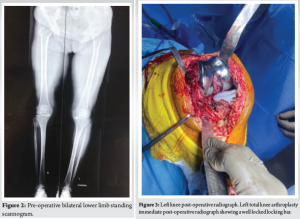

An 80-year-old female presented to our outpatient department with bilaterally painful knees, diagnosed to have bilateral tricompartmental knee osteoarthritis (Fig. 1 and 2) without any comorbidities. The patient was operated for bilateral TKR in staggered manner 2 weeks apart with the left side being operated first. Both the knees were operated with Zimmer-Biomet CR vanguard prosthesis with 10 mm polyethylene insert being used on both the sides (Fig. 3 and 4). The post-operative course was uneventful with patient achieving full range of motion (ROM) 0–120°. The follow-up of the patient at 3 and 6 months was unremarkable as well, with patient being able to carry out her daily activities unassisted.

One year postoperatively patient presented with localized painless swelling over medial aspect of knee associated with palpation of hardware, which was first noticed by the patient 4 months back not associated with any trauma and has remained constant since then. On examination, the patient had mild discomfort – with maintained ROM up to 120°. There was a small, localized swelling over medial aspect of knee, which, on superficial palpation, revealed impinging hardware (Fig. 4). Radiographs (Fig. 5) demonstrated the backing out of the locking clip, which is inserted in a medio-lateral manner to keep the polyethylene insert in its place (linear locking mechanism using tongue and groove), with the polyethylene insert being in its place. Immediate post-operative radiographs and radiographs taken at follow-up were examined to confirm the correct initial position of the locking clip.